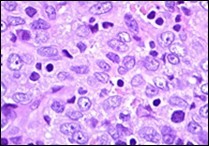

Ultrastructural evaluation is devoid of pertinent cellular features. However, modified endothelial cells, smooth muscle cells, striated muscle cells, histiocyte- like cells, fibroblast- like cells and miniature, interdigitating cellular processes conjoined by desmosome- like junctions are discerned5, 6. Figure 1, Figure 2, Figure 3, Figure 4, Figure 5, Figure 6, Figure 7, Figure 8.

Figure 3.Angiomatoid fibrous histiocytoma enunciating elliptical and spindle-shaped cells with moderate eosinophilic cytoplasm and intermixed lymphocytes and plasma cells 10.